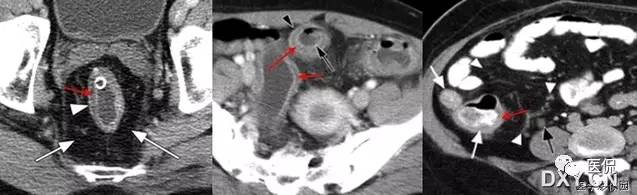

是肠套叠最常见的特征性CT征像,为肠套叠长轴与CT扫描层面垂直时的表现,反映了套叠的各层肠壁、肠腔及肠系膜间的关系。典型排列为自外向内分别代表鞘部外层肠壁、鞘部肠腔内造影剂、鞘部内层肠壁、偏心性套入部肠系膜、套入部肠壁、套入部肠腔内造影剂。:

肠套叠是指一段肠管及与其相连的肠系膜(套入部)被套如其相连的一段长管内(鞘部),导致肠内容物通过阻碍。婴儿由于大肠与小肠管径之比例相差大。故小肠易陷入大肠而被套牢。少数肠套叠可能来自某些器质性病变如美凯尔憩室、肠息肉、异位胰腺小结、血管瘤、异物、复制肠管、淋巴增生、肿瘤、寄生虫等,其中以美凯尔憩室最多,过敏性紫斑也常会合并肠套叠,大于2岁的小孩发生肠套叠,一定要考虑到这些病变。大于5岁的病例中,则以淋巴瘤为最多;成人肠套叠小肠多见,常伴发良性病变;结肠型肠套叠则更多由恶性病变继发。良性病变有脂肪瘤、平滑肌瘤、血管瘤、神经纤维瘤、腺瘤样息肉、美克尔憩室、术后粘连机场动力性病变等;恶性病变有转移瘤、腺癌、类癌、淋巴瘤及平滑肌肉瘤等。由于肠套叠长轴与CT扫描层面的角度不同,表现各异。如扫描层面和迂曲的肠道相平行时,表现为彗星尾征或肾形征:即套叠近端肠系膜血管牵拉聚拢的征象。一般情况下,慧星尾征均与肾型肿块相伴出现。该肾形肿块为套鞘部游离缘与套入部近端肠管及肠系膜的CT斜切面图像,其中游离的套鞘呈弧形围绕套入部,形状若肾轮廓外形,而套入部近端肠管、肠系膜形状若肾蒂。此时,所谓慧星尾征的组成还应包括套入近端肠管。如果套叠的肠管与CT扫描垂直,则呈靶形征,即肿块影表现为圆形或类似环形。通常在肿块内可分辨出层样结构,推测可能是继发于套入部和鞘部间的液体或是肠壁水肿造成密度对比,类似同心圆形;当套入部肠壁显著水肿坏死或套入部肿瘤周围浸润累及肠系膜,肠系膜血管及脂肪、套叠时间较长,套入部系膜血管受挤压时,静脉血液回流障碍,套入部肠壁充血水肿、变硬,形成不完全性肠梗阻,套叠以上肠管蠕动增强,可引起代偿性肠管扩张肥厚,并可见肠系膜连同其血管纠集、扭曲,形成“漩涡征”。

肠套叠形成的“靶征”

扫描层面和迂曲的肠道相平行时,表现为彗星尾征或肾形征:即套叠近端肠系膜血管牵拉聚拢的征象。